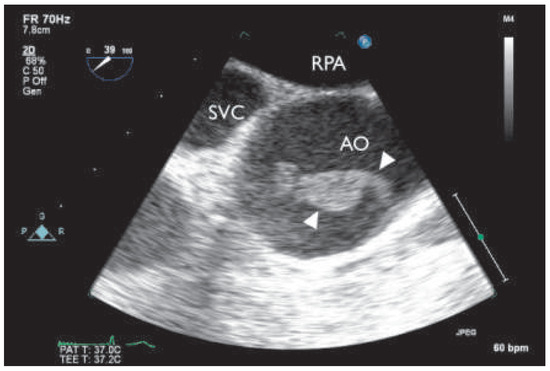

To avoid any further thromboembolic events, we decided to submit the patient to surgery and performed supracoronary ascending and hemiarch replacement in moderate hypothermic circulatory arrest; bypass grafting to the circumflex artery was not possible owing to a completely thrombosed vessel. The excised aortic segment showed three mobile rubbery structures, adherent to the aortic wall, one at the large curvature proximal to the brachiocephalic artery and two at the level of the sino-tubular junction right above the left coronary ostia (Figure 3 and Figure 4). Histological analysis revealed layered thrombi adherent to an aortic wall with mild atherosclerotic changes. There was no evidence of malignancy.

Figure 4. Preparation of the ascending aorta with two thrombi attached to the wall (arrows).